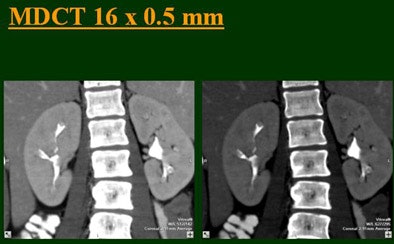

The single-row scanner required two breath-holds; the other scanners reduced scan time from about 20 seconds (four-slice) down to seven seconds (16-slice). Collimation for the single-row scanner was 5 mm, with 3-mm overlapping reconstructions. Collimation for the four-, eight-, and 16-row scanners was 2.5 mm, 1.5 mm, and 0.5 mm, respectively, with the patients scanned in a prone position.

Based on multiplanar reformatted (MPR) images, there was significant upscale improvement in calyceal detail from the isotropic images provided by single-detector scanning (median score 2) to four- (median score 3), eight- (median score 4), and 16-detector scanning, Raptopoulos said. On MPR images the calyceal were 1, 2, 3, and 5, respectively. The median ureteral filling was 4 for the upper and left-lower ureters, and 3 for the right-lower ureters.

A separate study Vrtiska presented at the RSNA meeting used a phantom with simulated contrast-filled ureters to compare the spatial resolution of their 64-slice CTU protocol to published protocols for other MDCT scanners, including four- and 16-slice scanners, as well as computed radiography images, which were reviewed by two gastrointestinal radiologists who scored each filling defect.

The 64-slice scanner, using 0.6-mm collimation and 0.3-mm reconstructions, was able to identify the greatest number of filling defects -- identical to computed radiography -- and was the only scanner/protocol to identify the smallest filling defects, the group concluded. "The resolution of 16-(slice) MDCT (1.25 mm/0.6 mm) was slightly less than 64-(slice) MDCT, and required longer scan times. The 4-(slice) MDCT was the most limited in resolution," Vrtiska and colleagues wrote in their abstract.